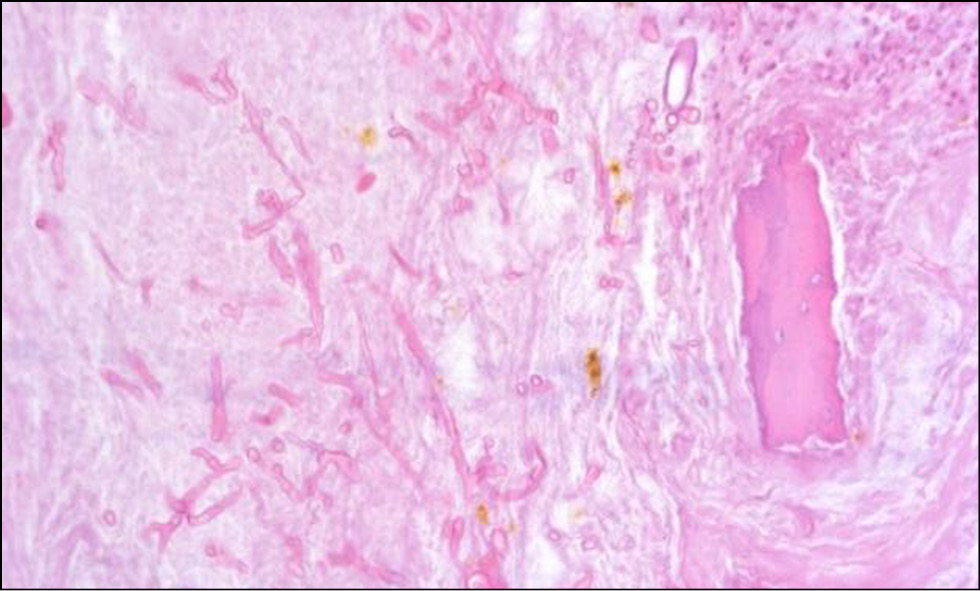

Для оценки патологического процесса исследован материал, взятый из некротизированных участков. Образец ткани фиксирован в 10%-м растворе забуференного формалина. Костные фрагменты после фиксации декальцинировались 1 сут в электролитном декальцинирующем растворе соляной и муравьиной кислот. Процессинг материала (обезвоживание, обезжиривание и пропитка парафином) осуществлен с применением автоматического вакуумного гистопроцессора Leica ASP200, образец залит в парафиновый блок с помощью станции заливки Thermo Scientific HistoStar, на ротационном микротоме Leica RM2265 изготовлены срезы с парафинового блока толщиной 4 мкм, окрашены гематоксилином-эозином по стандартной методике, а также ШИК-реакцией (PAS) и импрегнацией серебром по Грокотт для обнаружения мицелия грибов. Оценка окрашенных микропрепаратов проводилась методом световой микроскопии с использованием микроскопа Zeiss AxioLab.A1.

В полученных срезах визуализировались фрагменты (рис. 13) некротизированной слизистой оболочки (безъядерный эозинофильный субстрат с очертаниями предсуществующих структур) с наложениями детрита, распадающихся нейтрофилов, базофильных колоний микроорганизмов, раздробленных широких лентовидных гифов грибов, местами ветвящихся под прямым углом (рис. 14), и фрагменты костной ткани с широкими костно-мозговыми полостями, заполненными клеточно-тканевым детритом, распадающимися нейтрофилами, базофильными колониями микроорганизмов, раздробленными широкими лентовидными гифами грибов аналогичного вида (рис. 15), дающих положительную реакцию при окраске по PAS (рис. 16) и Грокотт (рис. 17).

Рис. 15. Окраска — гематоксилин и эозин. 200×. Справа имеется фрагмент разрушенной костной балки, в центральной части среди клеточно-тканевого детрита определяются мицелий гриба и гранулы гемосидерина

Рис. 16. Окраска — ШИК-реакция (PAS). 200×. В центральной части — мицелий гриба, дающий положительную реакцию